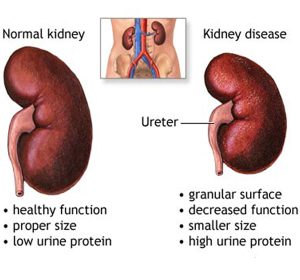

Kidney stones are hard masses that can grow from crystals forming within the kidneys. Doctors call kidney stones “renal calculi,” and the condition of having such stones “nephrolithiasis.”Most kidney stones are made of calcium oxalate. People with a history of kidney stone formation should talk with their doctor to learn what type of stones they have—approximately one stone in three is made of something other than calcium oxalate and one in five contains little if any calcium in any form. Calcium oxalate stone formation is rare in primitive societies, suggesting that this condition is preventable.1People who have formed a calcium oxalate stone are at high risk of forming another kidney stone.

Kidney stones often cause severe back or flank pain, which may radiate down to the groin region. Sometimes kidney stones are accompanied by gastrointestinal symptoms, chills, fever, and blood in urine.